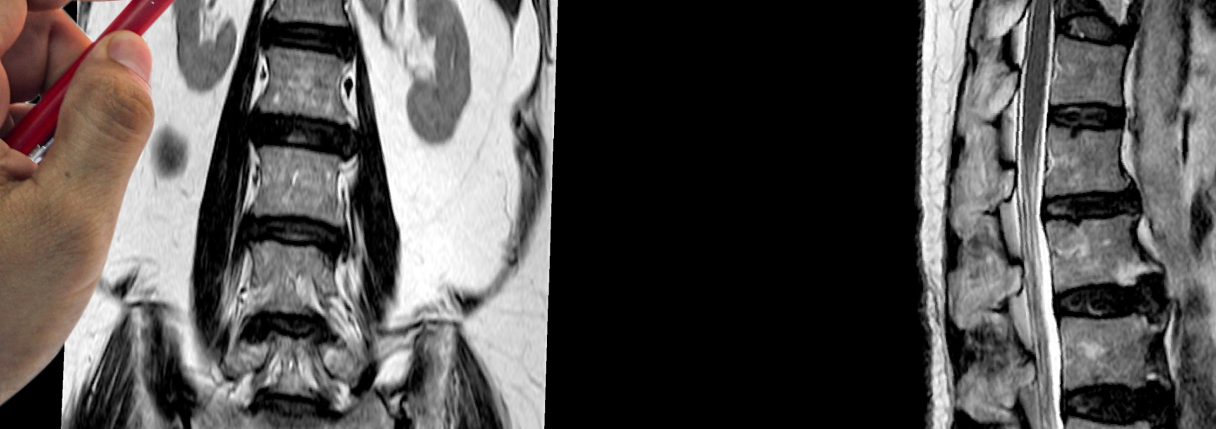

Esse método permite visualizar com clareza os discos intervertebrais, as vértebras, os nervos e os tecidos ao redor, revelando alterações que muitas vezes não aparecem em outros exames.

A ressonância da coluna lombar é um exame de imagem que utiliza campos magnéticos e ondas de rádio para produzir imagens detalhadas da região inferior da coluna vertebral, sem o uso de radiação ionizante. Essa técnica permite avaliar com grande definição as estruturas ósseas, os discos intervertebrais, a medula espinhal e as raízes nervosas.

O exame é indicado principalmente para investigar dores lombares persistentes, formigamentos, dormências, fraquezas nas pernas e alterações de sensibilidade. Por ser altamente sensível, é considerado o padrão ouro para o diagnóstico de doenças e lesões da coluna.

A ressonância da coluna lombar é o exame mais indicado para diagnosticar hérnias de disco, por sua capacidade de mostrar detalhes anatômicos com altíssima precisão. Ela permite diferenciar hérnias contidas, extrusas ou sequestradas e determinar o grau de compressão sobre as raízes nervosas.